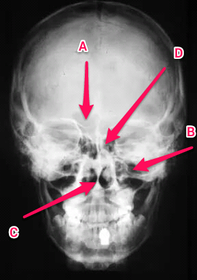

Anatomy practical midyear flashcard revision

anatomy

x-ray